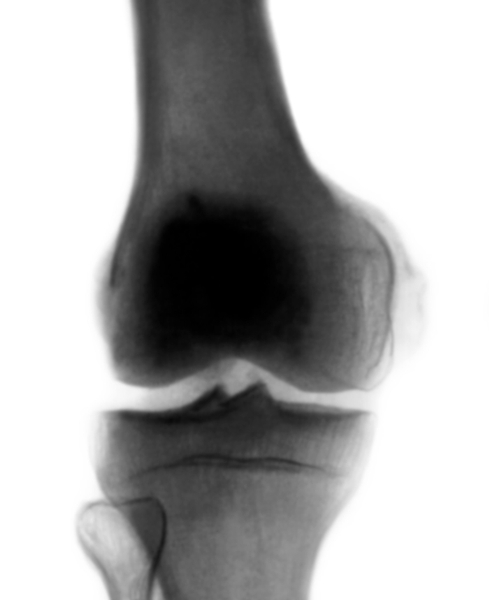

Болезнь Пеллегрини-Штида на рентгене (левый коленный сустав)

- Для подтверждения диагноза пациенту назначается рентгенографическое исследование одновременно в нескольких проекциях.

- При выраженном патологическом процессе на снимке четко визуализируются избыточные костные разрастания в области больного коленного сустава.

- С целью определения степени поражения требуется проведение МРТ и КТ. Обязательным является и анализ крови для определения количества кальция в организме.

В раннем периоде после травмы, когда клиническая картина идентична ушибу или дисторсии коленного сустава, а также при сочетании с внутренними повреждениями его диагностика затруднена. Через 3—4 недели после травмы на рентгенограммах коленного сустава определяют оссификат (рис.), имеющий вид скобки, серпа или неправильную форму, который отделен от надмыщелка бедренной кости полоской просветления. При отрицательных рентгенологических данных, но при наличии пальпируемого оссификата необходимо произвести рентгеновские снимки с внутренней или наружной ротацией конечности на 20° для устранения наслоения оссификата на контур мыщелка бедра. Информацию о степени зрелости оссификата может дать радионуклидное исследование. Дифференциальный диагноз проводят с отрывным переломом медиального надмыщелка бедренной кости, который выявляется на рентгенограмме сразу после травмы. Кроме того, краевой дефект надмыщелка по форме и размерам соответствует оторванному фрагменту кости. Похожую рентгенологическую картину можно наблюдать при перестроенном процессе в надмыщелке тракционного генеза, возникающем в результате многократных форсированных напряжений большой приводящей мышцы бедра, например у футболистов. Однако постепенное развитие этого заболевания, более молодой возраст, связь с занятиями спортом помогают уточнить диагноз.

Рентгенограмма коленного сустава (прямая проекция) при болезни Пеллегрини — Штиды: оссификация в области прикрепления большой приводящей мышцы бедра и медиальной коллатеральной связки коленного сустава к медиальному мыщелку бедра, а также по ходу связки.